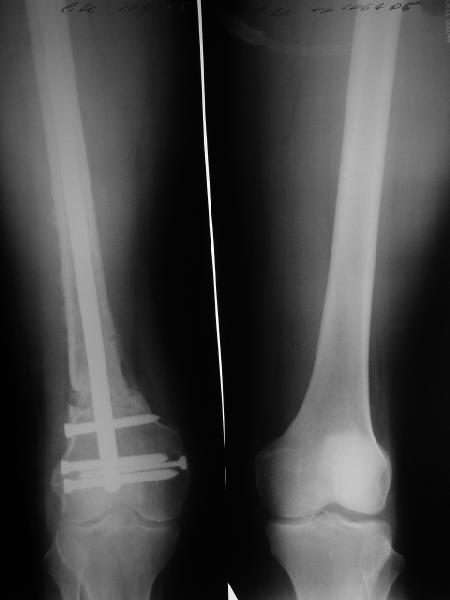

Пациенту М., 30-ти лет, 1,5 года назад в одной из московских больниц был выполнен остеосинтез бедренной кости штифтом UFN (диаметр штифта 9 мм).

К нам больной поступил с признаками ложного сустава бедренной кости, перелома

штифта и дистального блокирующего винта (images 1,2,3).